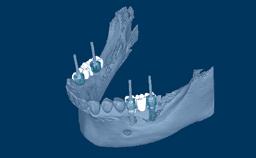

所有种植修复体的设计都应基于修复计划,并应满足所有相关的设计因素。大多数种植体固定义齿(或 FDP)的设计有许多共同点,以合理的设计遵循这些共同点很有帮助。第一要点是选择 FDP 的类型和方案。下一要点是选择固位方式,然后是考虑所需的外部和内部结构,以满足美观、功能和强度等因素。本模块将依次探讨每个设计要点。本网络学院设有单独且更详细的单元,将以现有模块为基础,阐述 FDP 修复材料、基台和种植体的选择。

- 修复体类型及缺牙修复方案